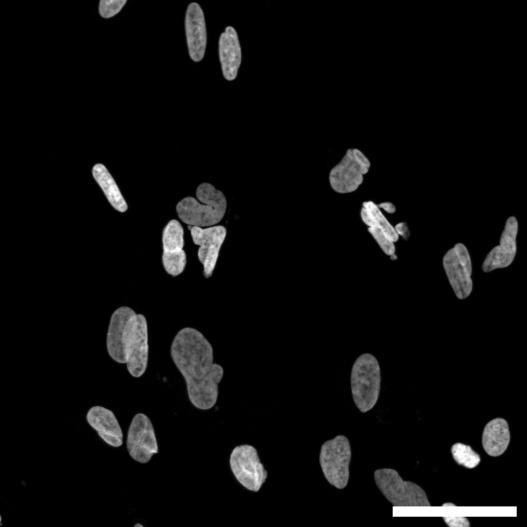

Calceinlabellingofneuron-astrocytecoculturesatmultipletimepointsshowedrobustcellviabilityandincreasedculturecomplexityovertime.

1week7weeks

Calcein